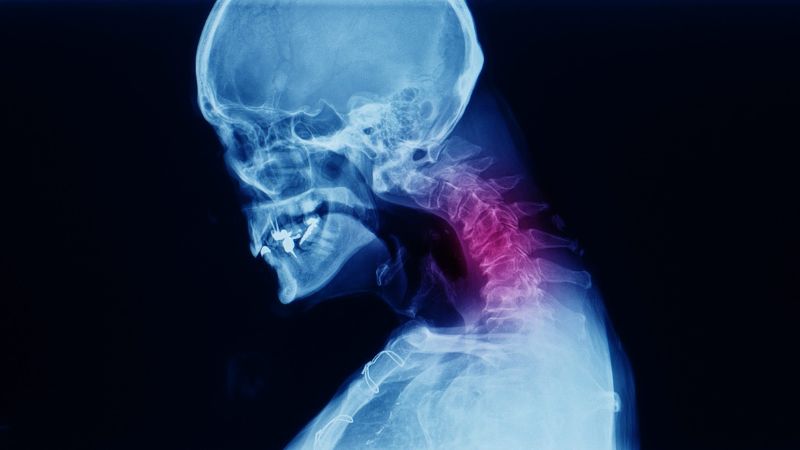

Are you looking for a solution for neck bone spurs? Bone spurs, or cervical spinal osteophytes, are a common condition that can lead to chronic neck pain, stiffness, and limited movement. Fortunately, surgery or long-term use of medication is not the only solution. This article by Docosan offers a comprehensive guide to physical therapy for cervical spinal osteophytes – a non-invasive and effective approach to relieve discomfort and improve your quality of life. For those seeking natural and sustainable care, this is essential information.

Physical therapy for cervical spinal osteophytes is widely recognized as one of the most effective and safe treatment methods available. It not only addresses the symptoms but also helps manage the condition at its root. Through targeted exercises, manual therapy, and modern therapeutic techniques, physical therapy provides long-term relief without the need for surgery or drugs. The key benefits of physical therapy for cervical spinal osteophytes include: